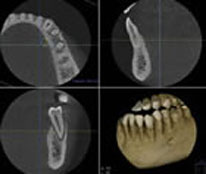

例えば、インプラント手術において危険領域となる神経管や血管の位置や骨幅、骨質などを正確に診査・診断するためにはCTによる精密検査は欠かすことはできません。

CTによる精密検査の結果、最終上部構造装着時のベストポジションの想定や不必要な骨移植・骨造成の回避、そして、フラップレス術式やイミディエイト術式が可能かどうかの判断ができるため、理想的な治療計画がたてられます。

さらに、CTデータを元にしてコンピュータ上でシミュレーションすることができるのも大きな利点といえます。